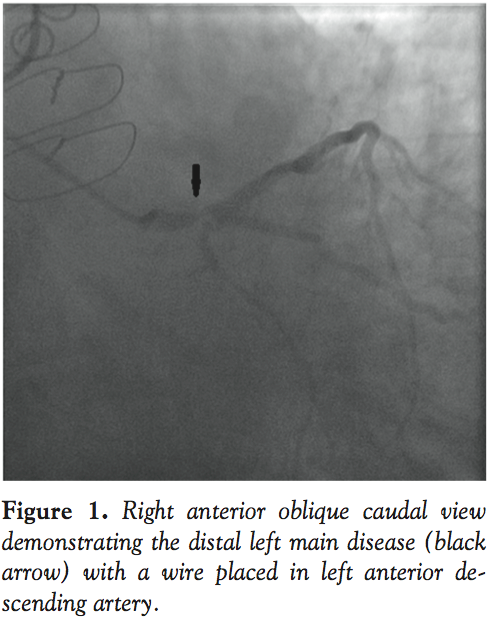

Attempt to obtain arterial access via femoral route through pre-existing aorto-femoral bypass graft bilaterally was unsuccessful. Using a left brachial approach, coronary angiography revealed severe distal left main stenosis (75%) extending into the proximal left anterior descending (LAD) artery (Figure 1), a patent large intermediate ramus was patent; and chronic total occlusion of a large obtuse marginal branch and right coronary artery. All bypass grafts were occluded. His balloon-pump assisted coronary intervention1 jeopardy score (BCIS-1) was 12 (maximum). Left ventricular end-diastolic pressure was 28 mm Hg. Abdominal aortography showed total occlusion of infrarenal aorta with total occlusion of aorto-bifemoral grafts (see Video 1 at www.invasivecardiology.com).Cardiothoracic surgery was consulted, but due to comorbidities, the patient was not deemed a candidate for repeat CABG. An upper extremity arterial duplex scan performed to ascertain that the left brachial artery was large enough to accommodate the IABP revealed a size of 5.8 x 6.2 mm.